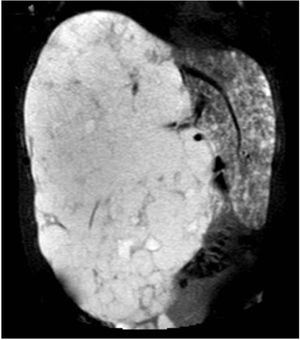

Hombre de 47 años, sin antecedentes, que consulta por dolor abdominal súbito. Se palpa hepatomegalia pétrea que ocupa ambos hipocondrios y llega hasta palas ilíacas, por lo que se realiza ecografía abdominal y posteriormente tomografía computarizada (fig. 1) con hallazgo de hepatomegalia de 37×29×23cm por lesión ocupante de espacio hepática en lóbulo derecho compatible con hemangioma cavernoso gigante. Se confirma con resonancia magnética con contraste (fig. 2), en que se objetiva que el resto del parénquima hepático está ocupado por incontables lesiones, sugerente de hemangiomatosis hepática con ausencia de parénquima hepático normal.